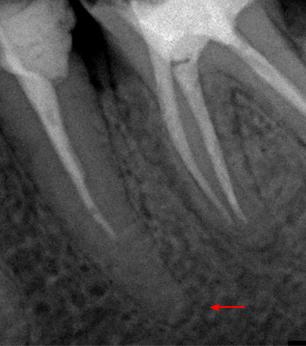

Пациент 45 лет направлен лечащим доктором на перелечивание 35 зуба.

Со слов пациента эндодонтическое лечение проводилось три года назад.

На рентгенологических снимках представлена картина до лечения, диагностический снимок и конечный результат.